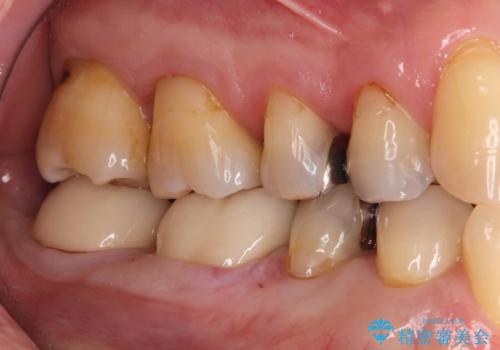

銀歯の下の虫歯|オールセラミッククラウン

まず既存の銀歯を除去し、虫歯を取り除いた後、オールセラミッククラウンで修復しました。

- 132,000円(仮歯:10,000円+オールセラミッククラウン 3年保証110,000円)費用は治療当時の料金となります